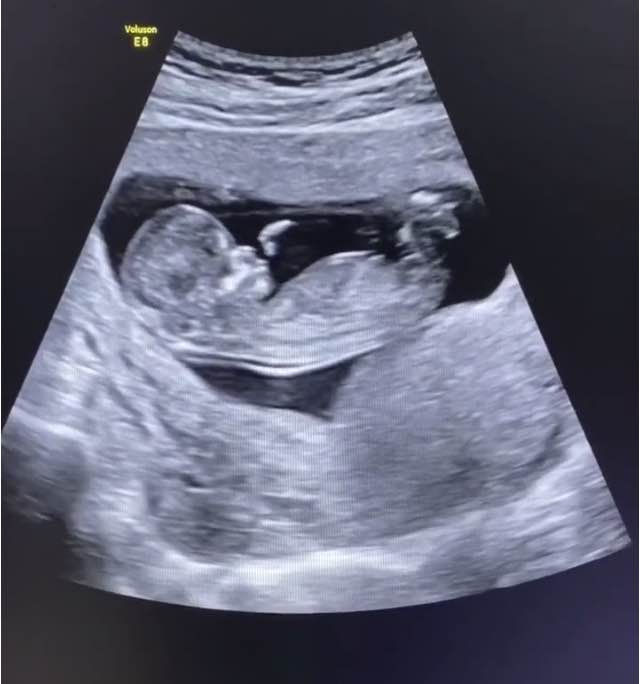

什么是NT检查?

说到NT检查,第一次听的孕妈妈都觉得很陌生,简单两个字母听组合的名称,听起来那么专业、难懂,其实NT检查就是一项应用B超检查的项目。

通过在B超下测量胎儿颈部透明层厚度(NT),根据测出的厚度进行判断,预测非整倍体染色体异常和其他的胎儿结构异常。注意:只是预测,这个检查不能作为疾病诊断手段。

NT检查又被很多人称为胎儿的第一次排畸检查,NT厚度通常与非整倍体染色体异常、遗传综合症、先天异常、先天性心脏病等相关,同时在检查中能发现某些胎儿大结构异常,如严重脑膨出、无脑儿、严重开放性脊柱裂、单心腔、严重胸腹壁缺损内脏外翻、致死性软骨发育不良等疾病。

NT检查需要获取胎宝宝的标准切面,这样才能保证检测结果的准确性。

如果检查时胎儿的胎头过仰或过曲或者处于趴着的姿势,都可能影响医生的判断。遇到这样的情况,医生会让孕妈妈改变体位,例如换成右侧卧位或左侧卧位,再重新测量。

并非胎儿处于趴着的姿势一定不能检测,若胎儿姿势良好,胎头不过伸、不过仰,可清楚显示颅内各层结构及鼻骨时,仍可继续进行NT检查。